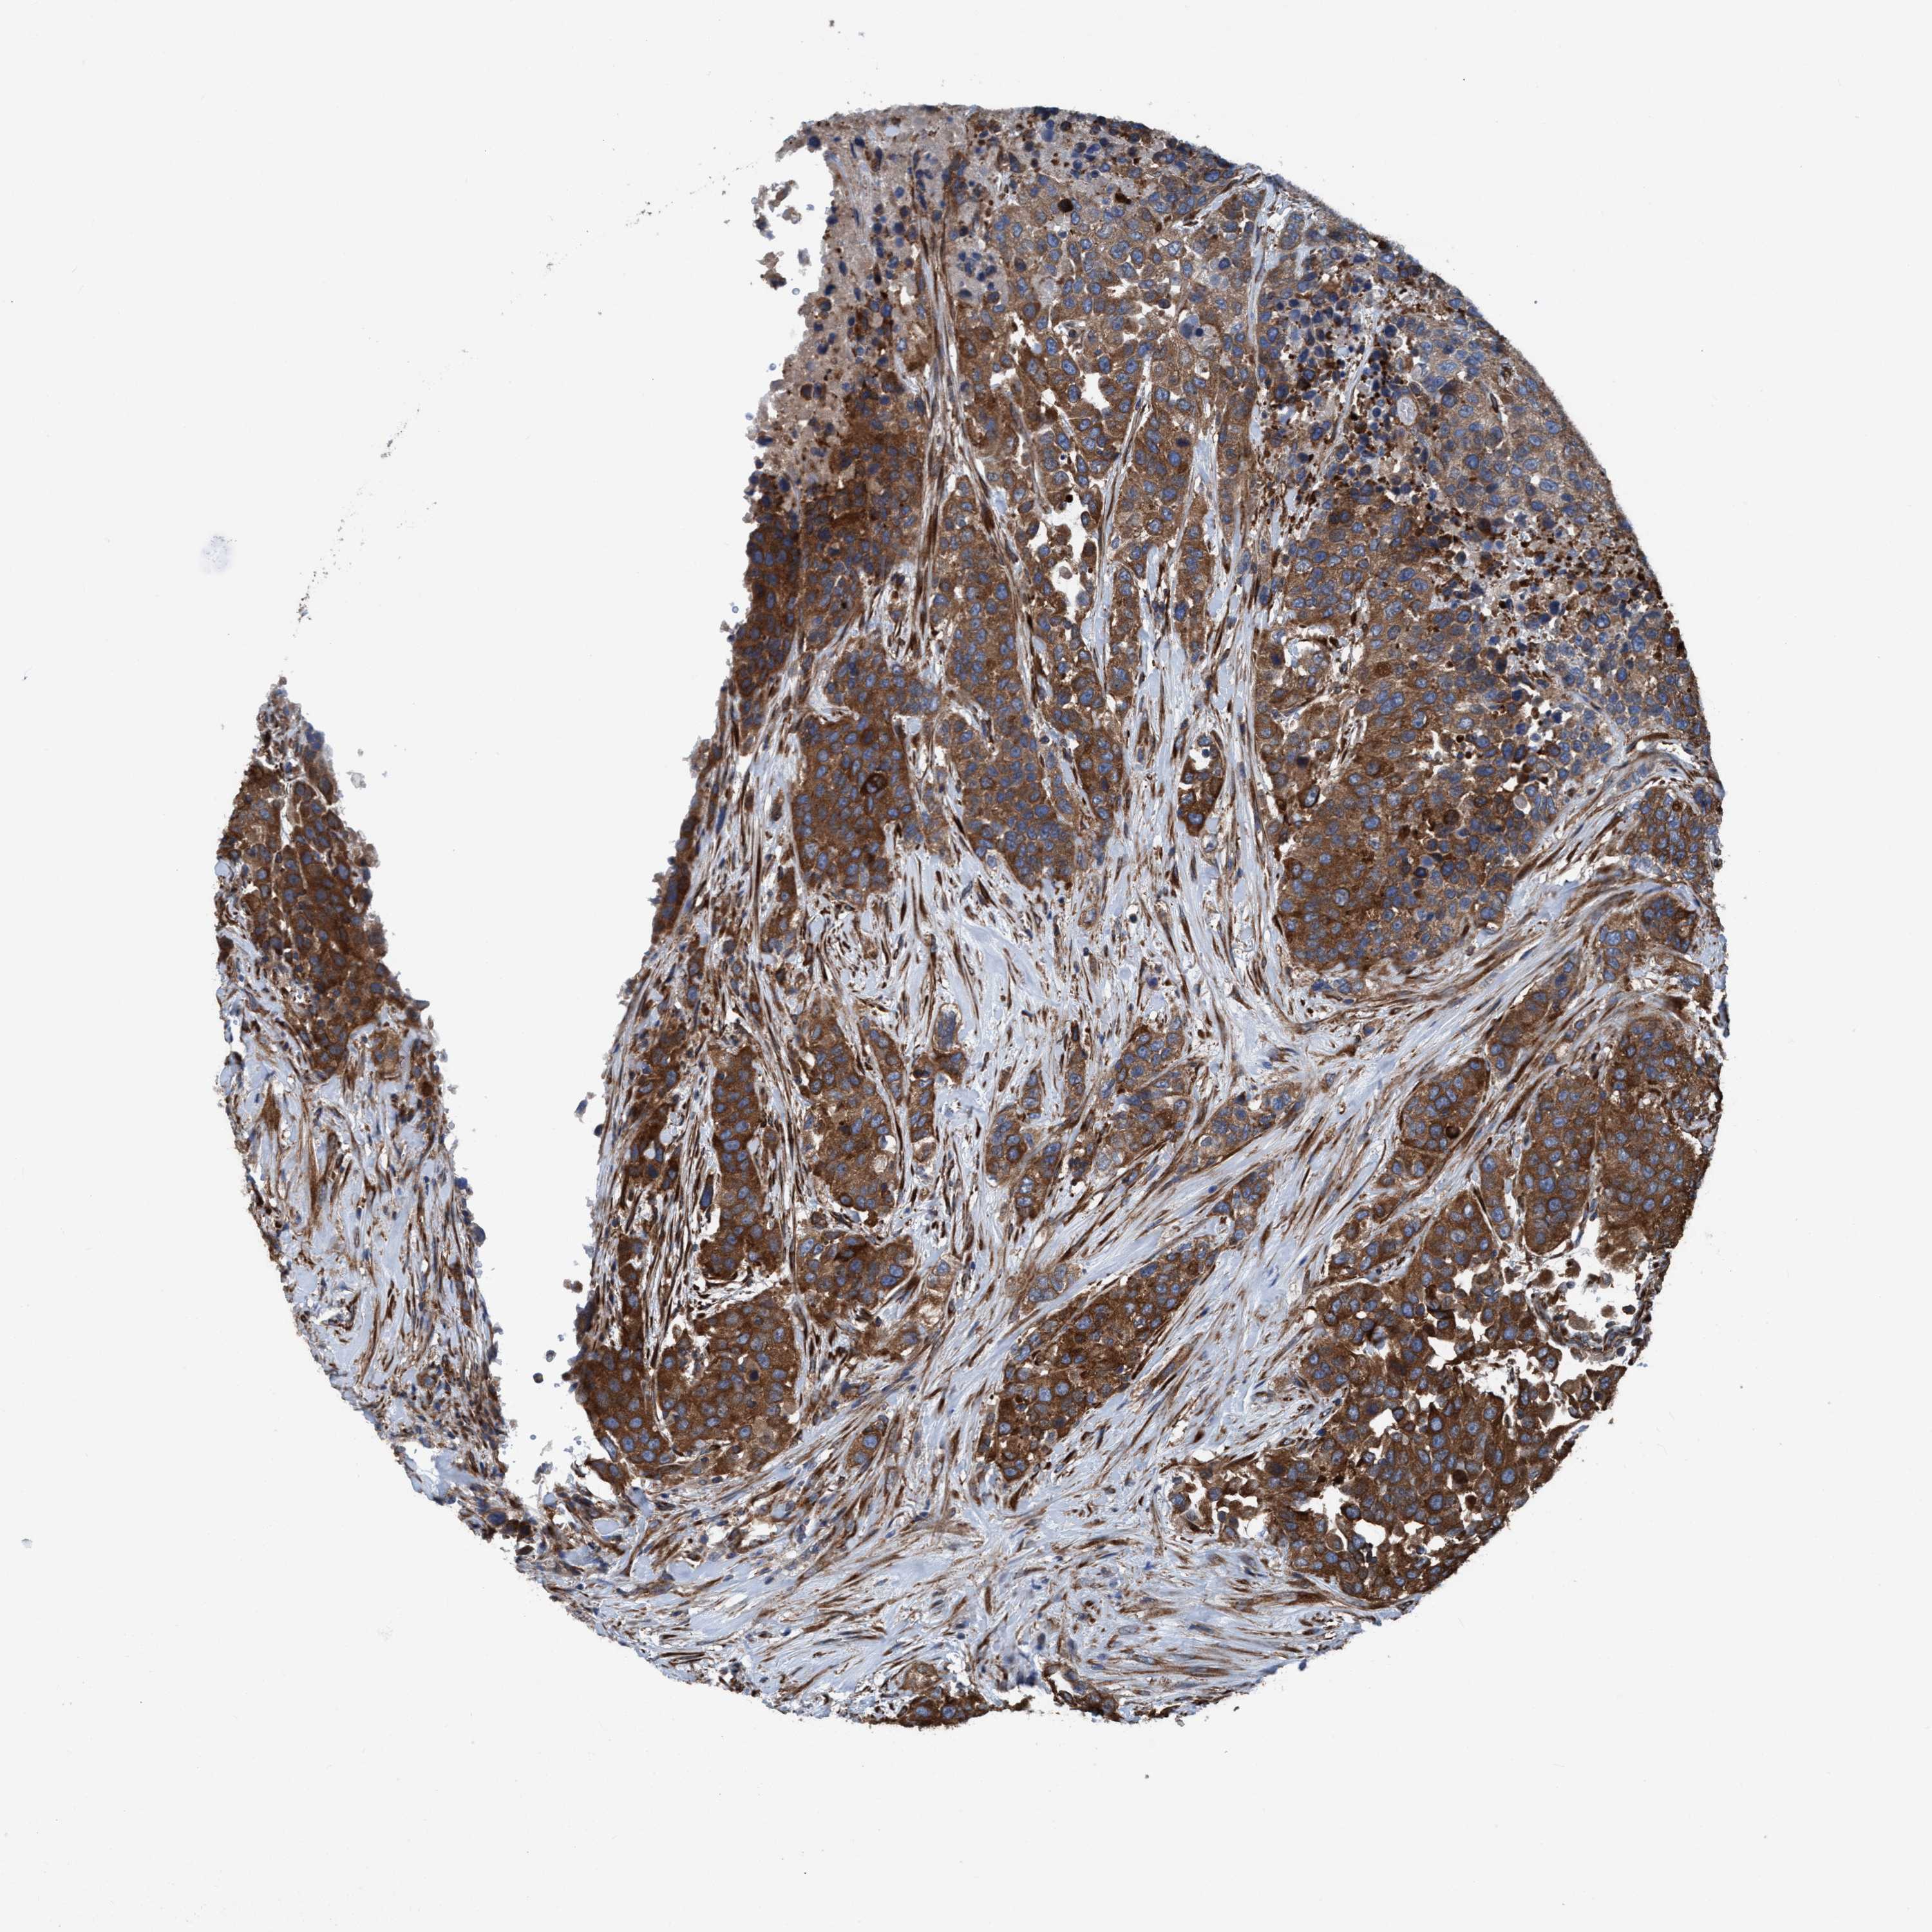

UROTHELIAL CANCER - Protein expressioni

A mouse-over function shows sample information and annotation data. Click on an image to view it in a full screen mode. Samples can be filtered based on level of antibody staining by selecting one or several of the following categories: high, medium, low and not detected. The assay and annotation is described here.

Antibody stainingi

Antibody staining in the annotated cell types in the current human tissue is reported as not detected, low, medium, or high, based on conventional immunohistochemistry profiling in selected tissues. This score is based on the combination of the staining intensity and fraction of stained cells.

Each image is clickable and will lead to virtual microscopy that enables deeper exploration of all samples and also displays staining intensity scores, fraction scores and subcellular localization as well as patient and tissue information for each sample.

Antibody HPA022949

Antibody HPA022963

Staining

High

Medium

Low

Not detected

Intensity

Strong

Moderate

Weak

Negative

Quantity

>75%

75%-25%

<25%

None

Location

Nuclear

Cytoplasmic/membranous

Cytoplasmic/membranous,nuclear

Urothelial carcinoma, Low grade

Urothelial carcinoma, High grade